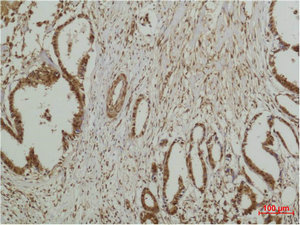

• Immunohistochemical analysis of paraffin-embedded human Breast caricnoma using ERK 5 Polyclonal Antibody.